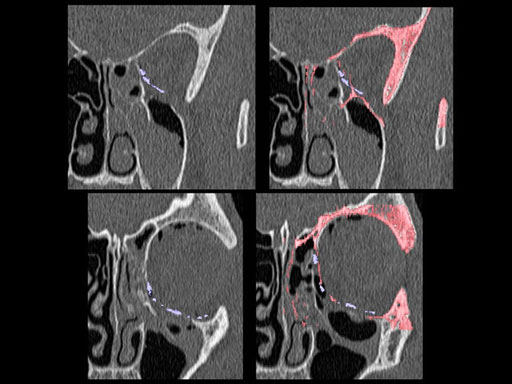

Furthermore, as orbital floor fractures are quite frequently associated with medial wall fractures; anatomic restoration especially in the transition zone between both wall is a demanding procedure. As described by B. Hammer, the orbital floor has an initial shallow convex section behind the rim, then inclines upward behind the globe, and inclines upward to meet the medial wall, creating a distinct bulge behind the globe. These convex curves of the medial wall and floor create a postbulbar constriction of the orbital cavity, which must be reconstructed when the orbit is rebuilt following fractures. Treatment is directed at precise anatomical reconstruction of orbital shape and volume in order to restore the correct position of the eye. To provide surgeons with an adequate implant that addresses the requirements of two wall acute orbital fractures or for secondary reconstruction of enophthalmos and dystopia, a new series of preformed orbital plates was developed for the new orbital matrix system.

These pre-formed orbital plates were developed based on the evaluation of more than 3000 CT scans of patient data and then reduced to 279 in order to find anatomical averages. In the end it was possible to reduce the number of plates down to two per side and still match the vast majority of all patients including males and females.

Unlike the existing two-dimensional mesh implants, the geometry of the new preformed plates will be adequate to match the individual anatomic situation of the patient in almost any case. However, the mesh parts can be individually adjusted if necessary. In these cases the solid part in the central posterior area needs to remain untouched. Areas of the orbit that do not require a bridging can be spared out by trimming the implant along the designated cutting lines in the height of the medial wall and/or length of the orbital floor area. The lateral anterior part of the plate is intentionally pre-bent higher than the orbital rim anatomy to allow free plate movement during plate positioning.

30 year old male patient with fracture of left orbital floor and medial wall.

Provided by Dr Dr Marc C Metzger, Freiburg, Germany.